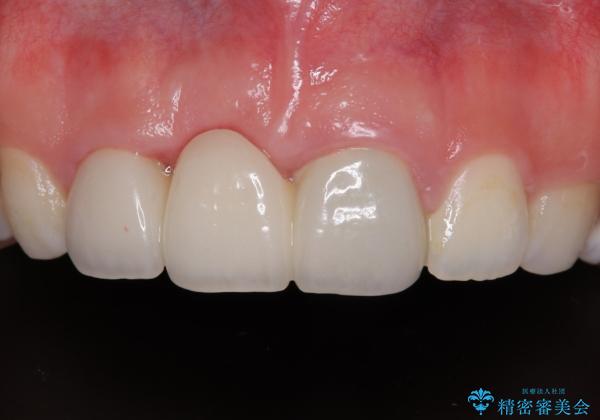

歯肉ラインを整えるために歯肉移植術を行うか悩んでいましたが、行わないという判断をされたため、やや不揃いの歯肉ラインとなりました。